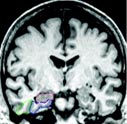

- MRI of the head: Magnetic resonance imaging (MRI) uses a powerful magnetic field, radio frequency pulses and a computer to produce detailed pictures of organs, soft tissues, bone and virtually all other internal body structures. MRI can detect brain abnormalities associated with mild cognitive impairment (MCI) and can be used to predict which patients with MCI may eventually develop Alzheimer's disease. In the early stages of Alzheimer's disease, an MRI scan of the brain may be normal. In later stages, MRI may show a decrease in the size of different areas of the brain.

A combined PET/CT exam fuses images from a PET and CT scan together to provide detail on both the anatomy (from the CT scan) and function (from the PET scan) of organs and tissues. A PET/CT scan can help differentiate Alzheimer's disease from other types of dementia. Another nuclear medicine test called a single-photon emission computed tomography (SPECT) scan is also used for this purpose.

Using PET scanning and a new radiotracer called C-11 PIB, scientists have recently imaged the build-up of beta-amyloid plaques in the living brain. Radiotracers similar to C-11 PIB are currently being developed for use in the clinical setting.

Images: Images are shown for illustrative purposes. Do not attempt to draw conclusions or make diagnoses by comparing these images to other medical images, particularly your own. Only qualified physicians should interpret images; the radiologist is the physician expert trained in medical imaging.